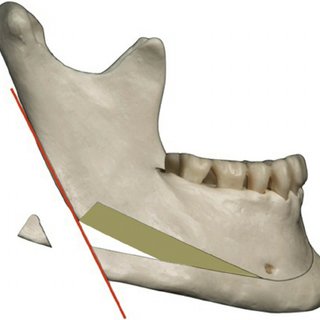

24. Chin wing osteotomy

24. Chin wing osteotomy